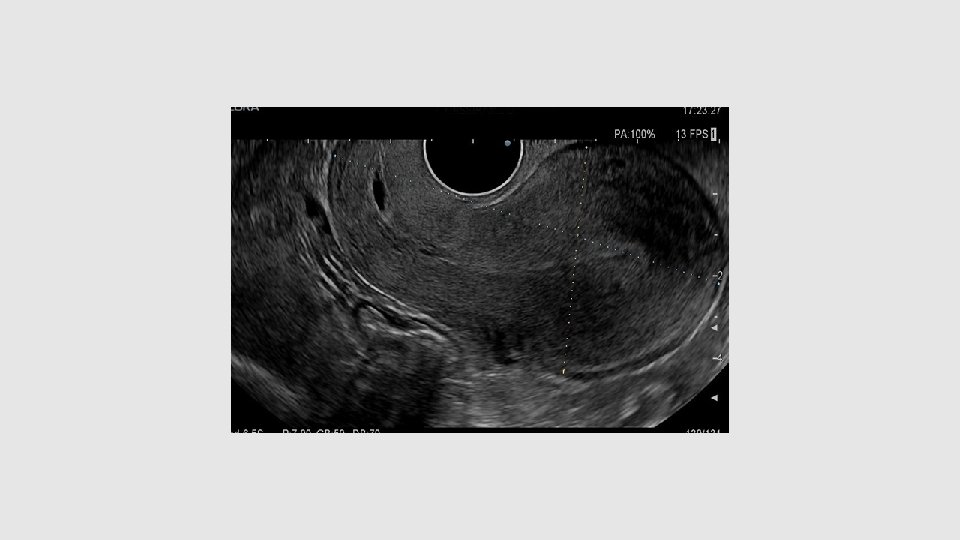

ECHO DE CONTRÔLE DE VACUITE UTERINE • Expulsion complète • Cavité vide (ligne de vacuité) , endomètre absent ou peu abondant, parfois hématométrie, parfois endomètre un peu épaissi avec petites zones hypoéchogènes (pouvant correspondre à débris sanguins ou déciduaux) • Grossesse persistante (1 à 5% des ivg med) • Rétention œuf mort : œuf non embryonné, non évolutif ou aspect d’œuf clair • Rétention ovulaire partielle: La présence d’une cavité épaisse homogène pouvant atteindre 15 mm est habituelle, et la présence de structures hyperechogenes intracavitaires n’est pas forcément synonyme de rétention (caduques ou caillots) bien qu’elle pose question. En revanche, la présence d’un signal doppler arteriel plaide en faveur d’une rétention DONC PAS DE SIGNAL DOPPLER ET <15 mm: RASSURANT

Rétention vascularisée

Malformation Artério veineuse (MAV)

Rétention de sang (hématométrie)